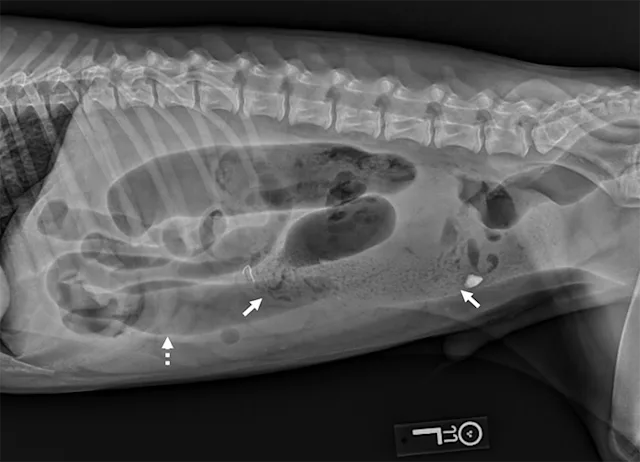

Left lateral image showing segmental dilated gas-filled intestines (dashed arrows) with heterogeneous soft tissue in a small intestinal segment (solid arrow) in a dog. The foreign material was cloth, and the diagnosis was small intestinal mechanical obstruction. Exploratory laparotomy was performed.